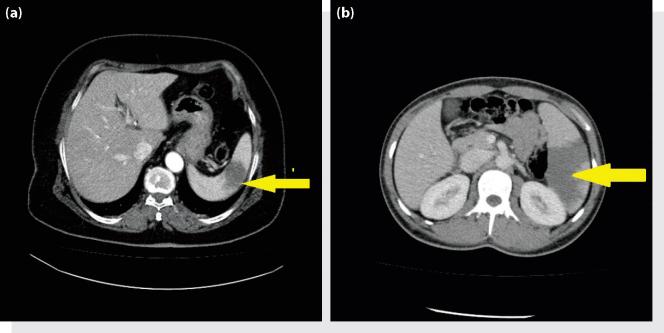

Splenic infarcts are rare cases. It may not be noticed in the emergency department because the clinical picture is likely to mimic various acute abdominal pains. The splenic infarct is often the result of systemic thromboembolism associated with cardiovascular disorders. The aim of this study is to present an evaluation of the patients that presented to the emergency department (ED) with abdominal pain and were diagnosed with splenic infarct.